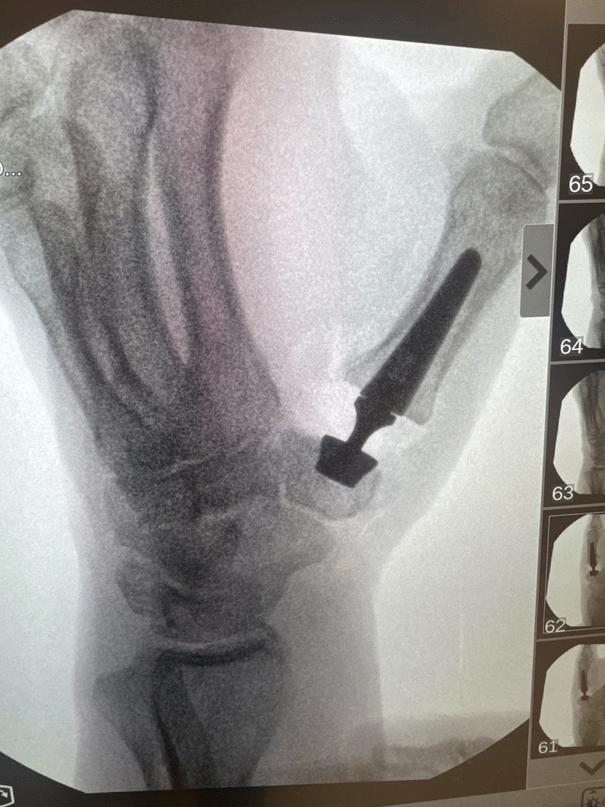

UCHealth physicians, including Dr. Catalano, Dr. Leversedge, Dr. Greyson and Dr. Belton at the University of Colorado Hospital, recently performed the first procedure of its kind in the western United States — a next-generation thumb arthritis surgery using a small prosthetic joint designed to improve outcomes for patients with severe thumb arthritis.

Unlike traditional surgery, which removes the arthritic joint and can result in prolonged pain, weakness, thumb collapse and lengthy recovery times, this innovative approach uses a Swissdesigned prosthetic ball joint — the Touch CMC 1 Dual Mobility Trapeziometacarpal Prosthesis. Dr. Catalano calls it “a hip replacement for a squirrel ” The implant preserves bone, maintains thumb stability, and eliminates the need for casting or K-wires. Surgical results in Europe, where the technique has been used since 2018, show a significantly less painful and faster recovery compared with traditional procedures.

The surgical team trained extensively in Europe and is now among the first in the country to offer the procedure as part of an FDA-approved clinical trial. Early results show patients going home the same day with minimal dressing, experiencing reduced discomfort, and regaining stronger thumb function more quickly. Many patients report improved pinch strength and greater overall hand function following the procedure.

Dr. Belton shares his personal insight on the Touch CMC 1:

"From my standpoint, CMC basilar thumb arthritis is one of the most common debilitating diseases of the hand without a perfect solution. Though previous surgeries have been helpful and have provided patients some relief, they are imperfect in that the recovery is prolonged and the construct does not reestablish the native architecture of the hand. Though those previous surgeries to date have been good, it is imperative upon us as academic surgeons to push the envelope and look for additional interventions that may benefit our patients. We had the unique opportunity of learning a new technique in Switzerland and France in early 2025, and Drs. Catalano, Greyson, and myself were impressed by the dual mobility prosthesis commonly performed by our European colleagues. Primarily, the decreased recovery period, the decreased post-operative pain, the lack for standardized occupational hand therapy and bracing, and the cosmetic reconstruction of the hand was something that we hoped to recreate in the United States.

The University of Colorado was chosen as a post-FDA approval study site allowing our department's hand surgeons to offer this surgery to our patients while studying surgical outcomes in US patients, replicating the preceding European trials. After months of training and surgical planning, our team (Drs. Catalano, Leversedge, Greyson, Belton) performed the first four CMC Touch One implant arthroplasties in Colorado and the entire Wet Coast. With initial success and burgeoning optimism, we will continue to shepherd this innovation across the US and provide an additional option for patients suffering from this disease. "